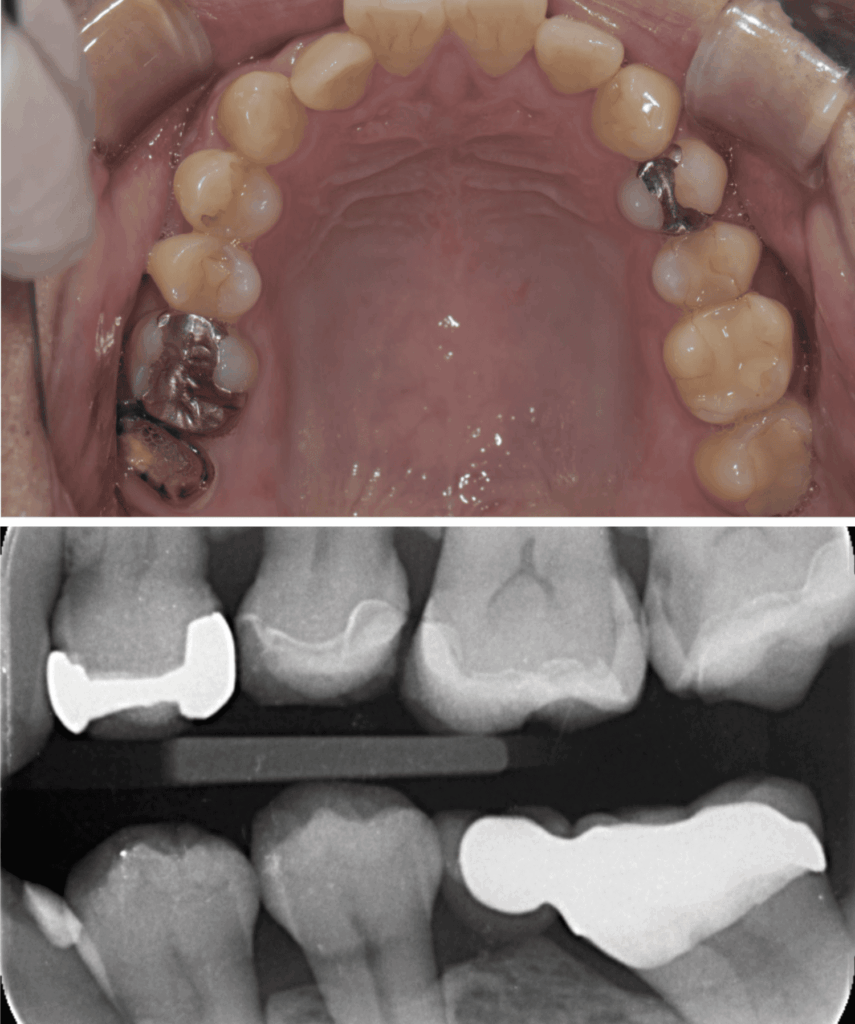

歯髄を温存し症状が出ないか1か月経過観察のためCRにて修復

お口の写真で青の部分があるのは、視覚的に保護剤と自分の歯がわかりやすいように区別するため一次的に青のCRを用いた

| 処置内容 (または主訴) | ①マイクロスコープによる根管治療 ②マイクロスコープによるう蝕除去およびセラミック修復 ③MTAを用いたマイクロスコープによる歯髄温存療法からセレック修復 |